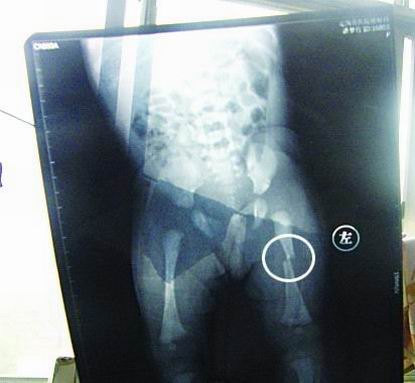

CT顯示小夢竹左下肢骨折

今年7月2日下午,定陶縣南王店鄉(xiāng)沈莊村孕婦聶元真,在定陶縣人民醫(yī)院剖腹產(chǎn)下一女嬰,取名為潘夢竹。醫(yī)院說,嬰兒出生后窒息,診斷為新生兒缺血缺氧性腦病,頭皮血腫。當(dāng)晚發(fā)現(xiàn)女嬰左下肢部位異常,第二天拍片顯示為左下肢骨干骨折。7月3日,潘夢竹的頭顱CT顯示其頭頂部骨折,蛛網(wǎng)膜下腔出血,顱內(nèi)血腫。